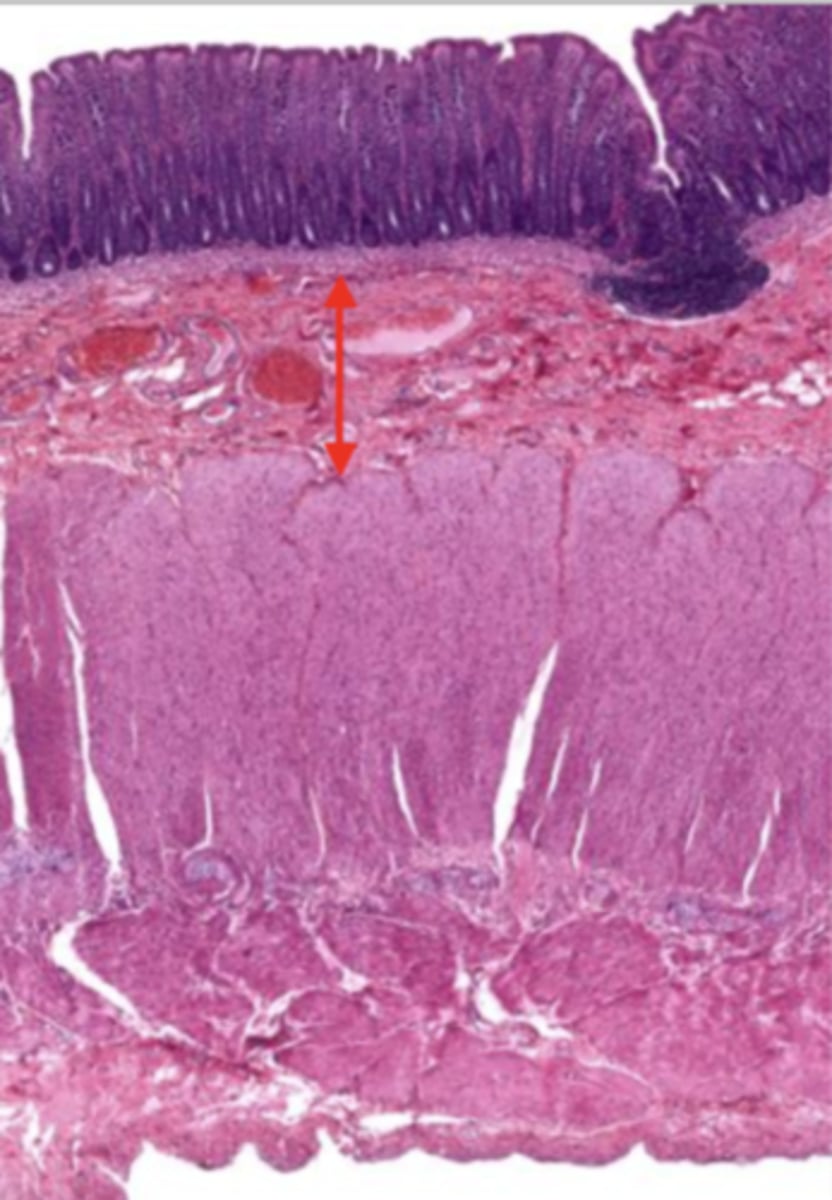

cardiac stomach (histology)

simple columnar epithelium

what kind of epithelium lines the mucosa of the cardiac stomach?

gastric pit (cardiac stomach)

lumen (cardiac stomach)

mucosa (cardiac stomach)

mucosal epithelium (cardiac stomach)

lamina propria (cardiac stomach)

muscularis mucosa (cardiac stomach)

submucosa (cardiac stomach)

contains glands and blood supply

muscularis externa (cardiac stomach)

serosa/adventitia (cardiac stomach)